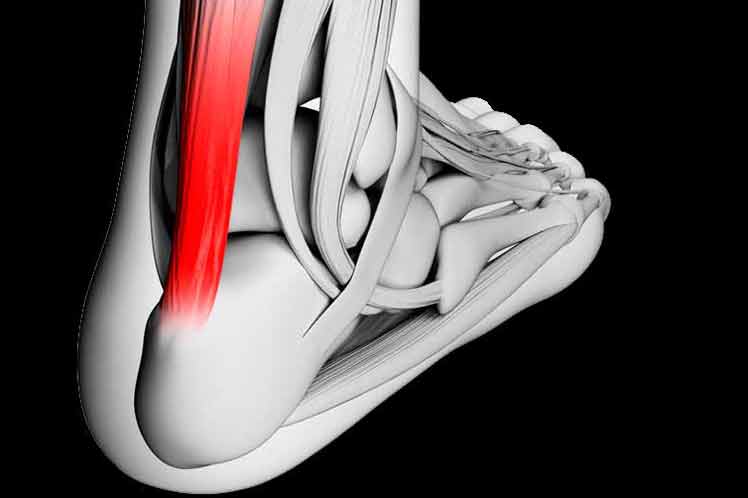

Estudiosos descubren el secreto del Tendón de Aquiles

Foto: CadenagramonteBerlín, 3 abr.- Científicos alemanes descubrieron que un tejido formado por fibras de proteínas extremadamente finas y resistentes hacen del Tendón de Aquiles el más fuerte del cuerpo humano, publicó la revista Nature Materials.

Foto: CadenagramonteBerlín, 3 abr.- Científicos alemanes descubrieron que un tejido formado por fibras de proteínas extremadamente finas y resistentes hacen del Tendón de Aquiles el más fuerte del cuerpo humano, publicó la revista Nature Materials.